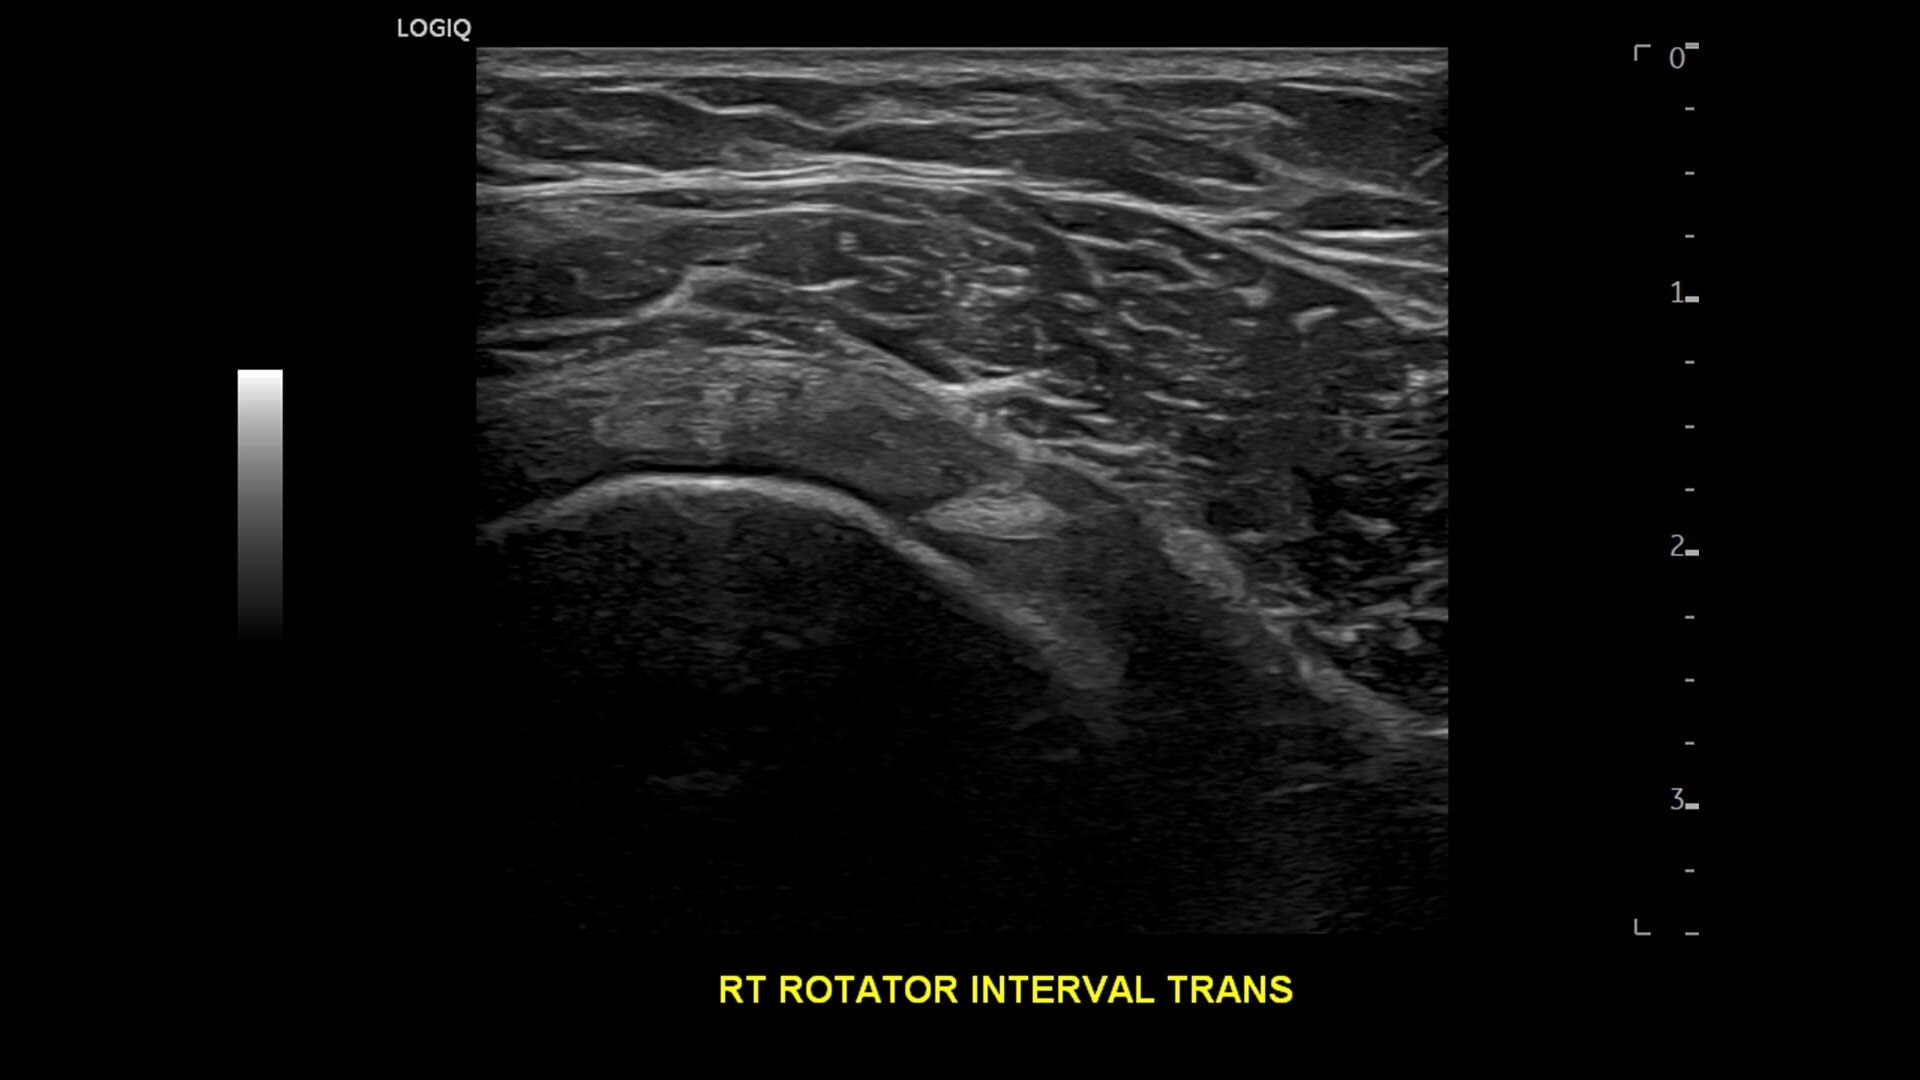

• cSound™ Architecture delivers exceptional clarity and resolution from near field to depth—with all pixels in focus

• Next‑level specialty and multi‑purpose probes—plus Pulsed Wave Doppler now available on the wireless Vscan Air™ CL —expand your clinical flexibility.

• Advanced flow modes give you the flexibility, from large vessels to fine microvascular detail, to visualize blood flow with precision